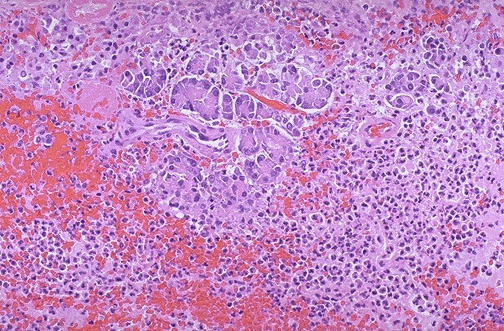

At high magnification, acute inflammation with necrosis and hemorrhage is seen with residual pancreatic acini in a case of acute hemorrhagic pancreatitis.